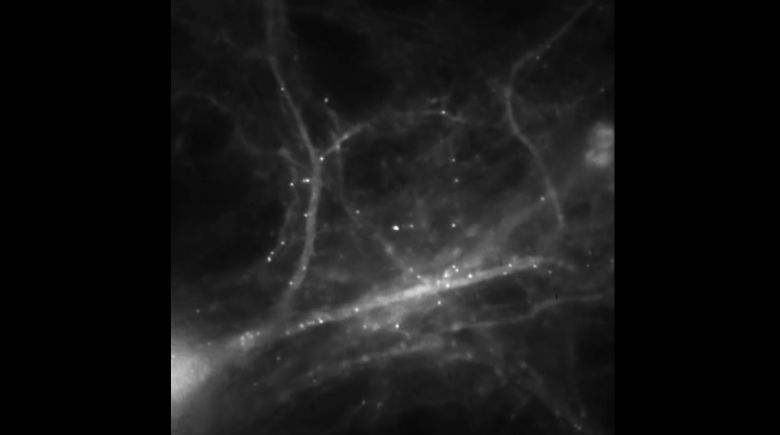

Poprzez śledzenie mRNA w komórkach mózgu, naukowcy uchwycili mózg wytwarzający wspomnienia (wideo)